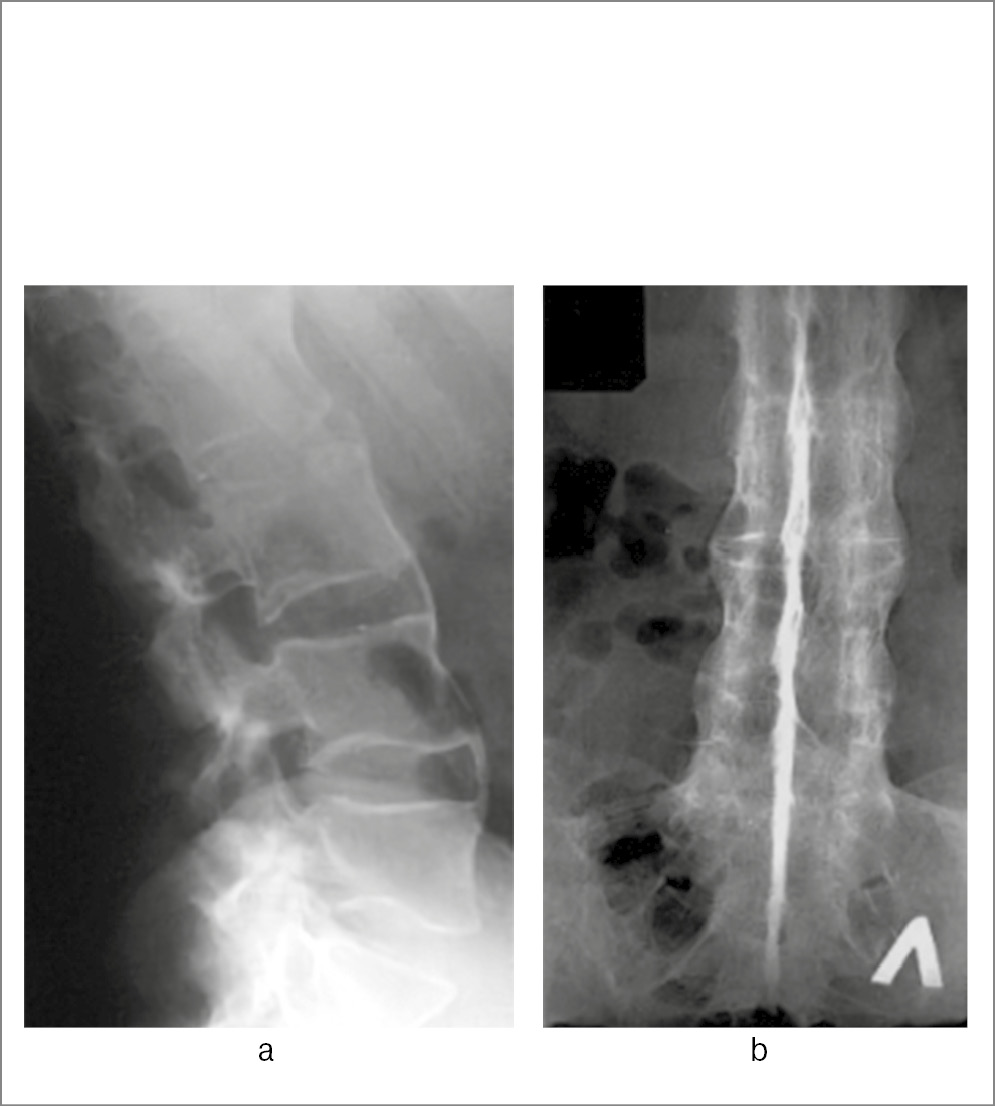

Спондилиты (спондилодисциты) могут вызываться и другими бактериями. Визуализационная картина в этих случаях не имеет каких-либо особенностей и не отличается существенно от туберкулезного или бруцеллезного поражения позвоночника (рис. 8).

Рис. 8. Пациентка Б., 33 года. Диагноз – остеомиелит тел позвонков LI и LII вероятно стафилококковой природы: a – рентгенограмма поясничного отдела позвоночника: деструкция смежных отделов LI и LII; b – МРТ (сагиттальная плоскость, режим Т2): дисцит в сегментах ThXII–LI и LII–LIII; c – МРТ (аксиальная плоскость, режим T2-STIR): паравертебральное жидкостное образование размерами 2,3×1 см (стрелка) в области левой подвздошно-поясничной мышцы (натечник).